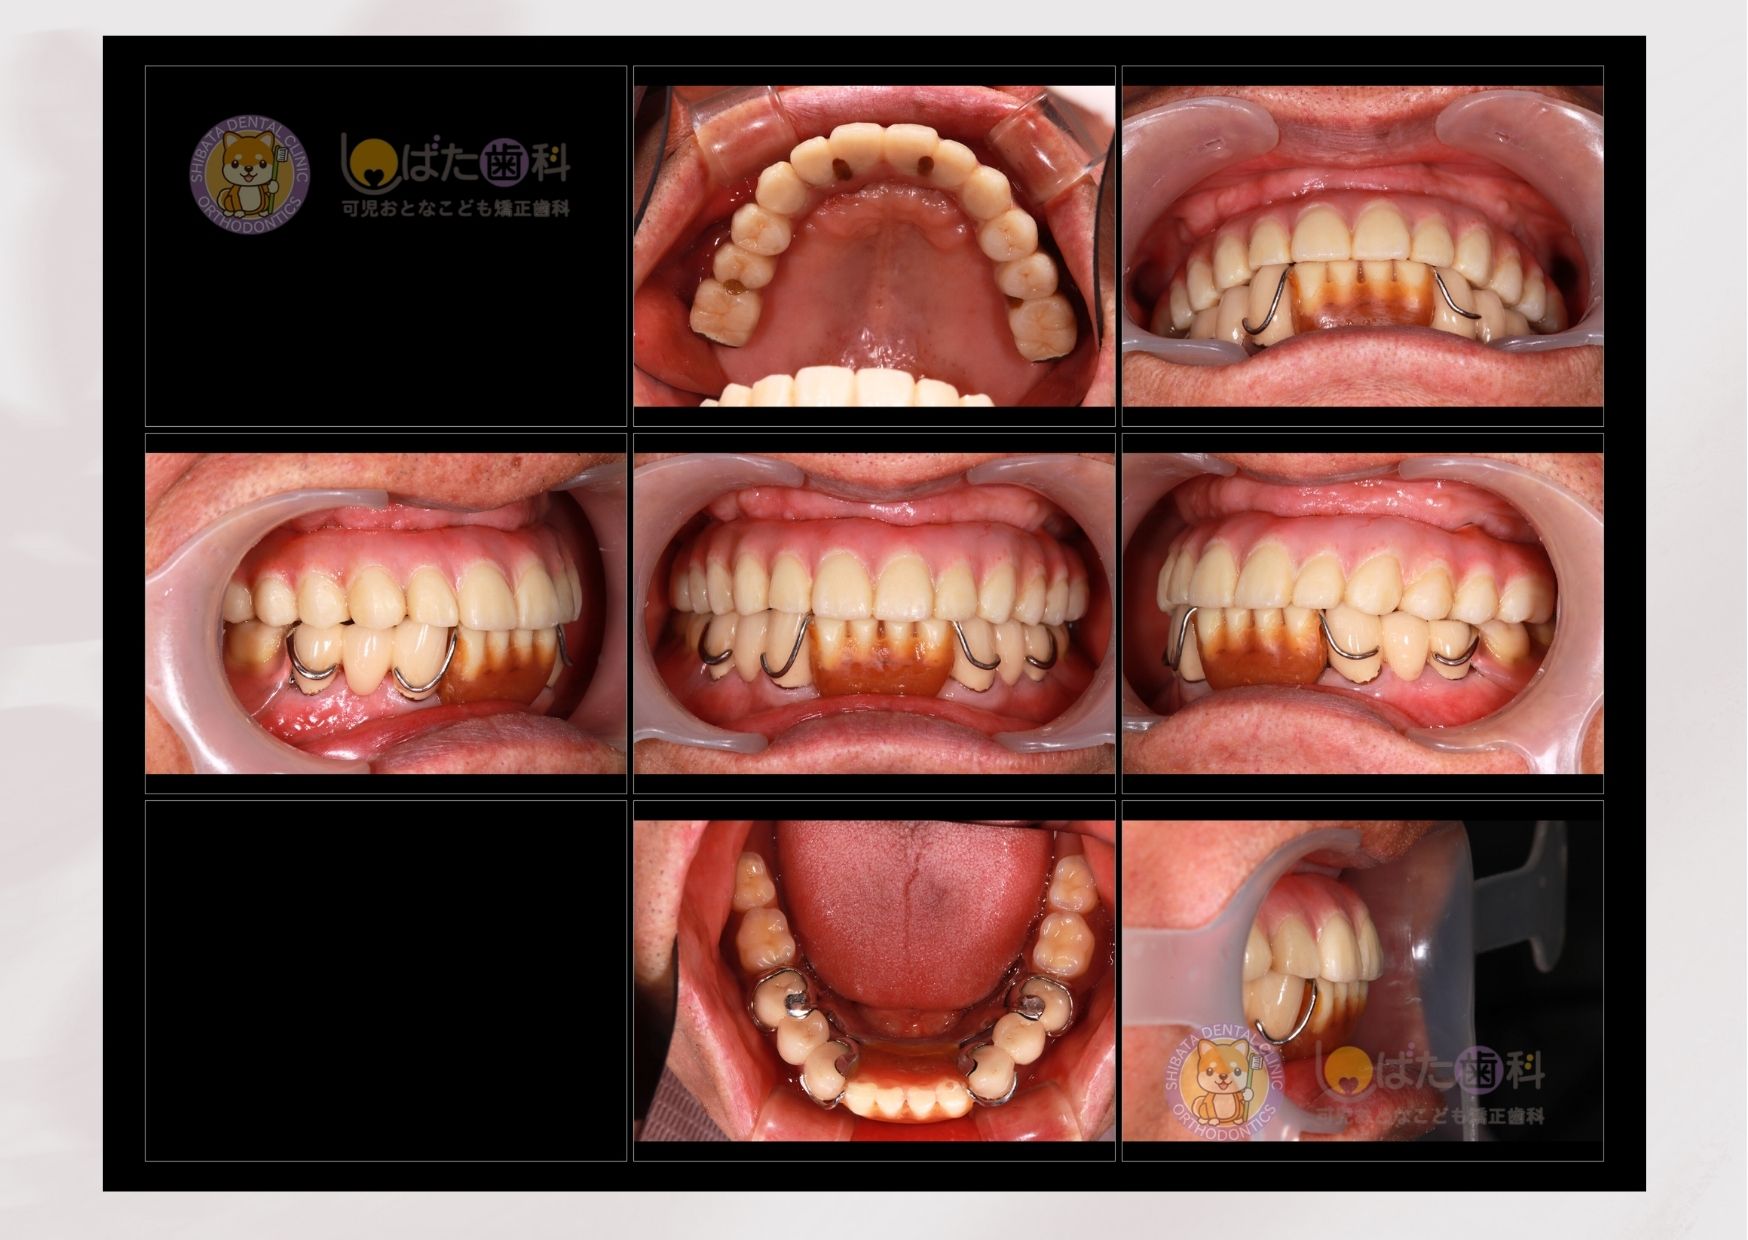

下記は、その一例です。50代女性の患者さんです。

長年原因不明の頭痛に悩まされ、医科に受診ても改善が見られないということでした。きっかけは10年前に入れた銀歯が外れてしまったところからでした。そのまま付け直してもよかったのですが、全顎的な診断をお伝えしたところこの際に全て整えたいということで矯正、インプラントの組み合わせで治療を行いました。

矯正治療の中盤で患者さんからこんな一言が。

「あの、最近、頭痛がなくって。そういえば薬も飲んでないかも」と。

歯並びが改善され、正しい噛み合わせなったことで慢性的に悩んでいたことが改善されたとのことでした。